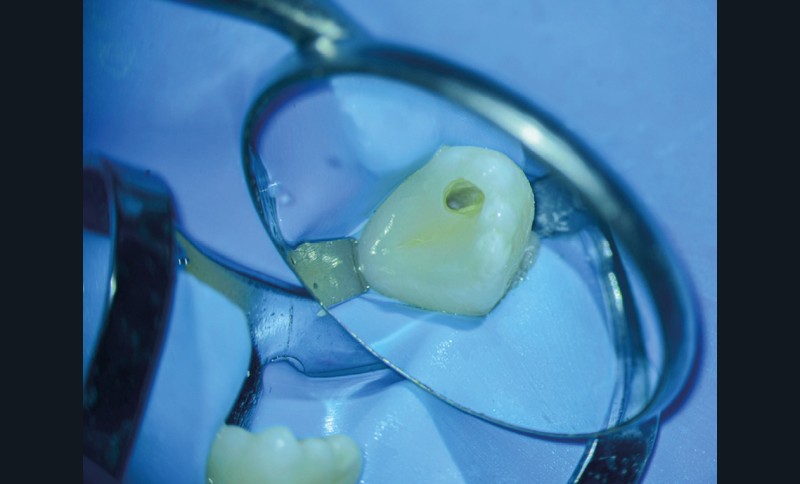

Lors du traitement endodontique, un suintement important étant encore présent à la fin de la seconde séance. J’ai pris la décision d’irriguer la crypte osseuse et sa lésion à travers la fistule à l’aide d’iso-bétadine délivrée par une aiguille stérile. C’est par empirisme que je réalise cette manœuvre ayant déjà montré à chaque reprise des résultats cliniques positifs. C’est l’équivalent d’une décompression sans tous les désavantages de cette dernière (fig. 4 et 5).